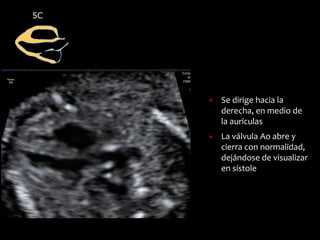

Cinco cámaras

5C

▪ Se dirige hacia la

derecha, en medio de

la aurículas

▪ La válvula Ao abre y

cierra con normalidad,

dejándose de visualizar

en sístole